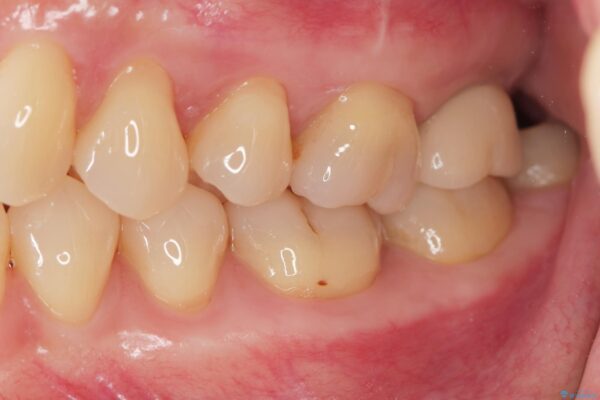

治療前

【噛むと歯が疼く】歯牙破折からのインプラント治療 治療前画像 【噛むと歯が疼く】歯牙破折からのインプラント治療 治療前画像 【噛むと歯が疼く】歯牙破折からのインプラント治療 治療前画像 【噛むと歯が疼く】歯牙破折からのインプラント治療 治療前画像 【噛むと歯が疼く】歯牙破折からのインプラント治療 治療前画像 【噛むと歯が疼く】歯牙破折からのインプラント治療 治療前画像 【噛むと歯が疼く】歯牙破折からのインプラント治療 治療前画像